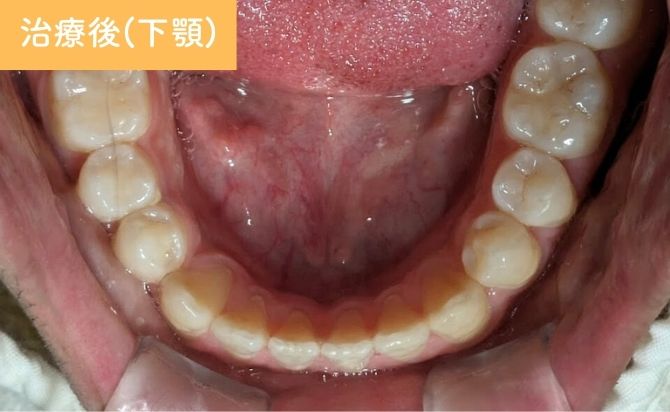

歯並びの変化(下)

治療終了時には、上顎前歯の歯間空隙が閉鎖され、前歯部の開咬も改善しました。上下前歯の前突感が軽減され、歯列弓も自然な形態に整っています。

前歯部の見た目が大きく改善しただけでなく、噛み合わせも安定し、機能面・審美面の両立が図られた症例となりました。

現在は、後戻り防止のためリテーナー(保定装置)を使用していただき、経過観察を続けています。